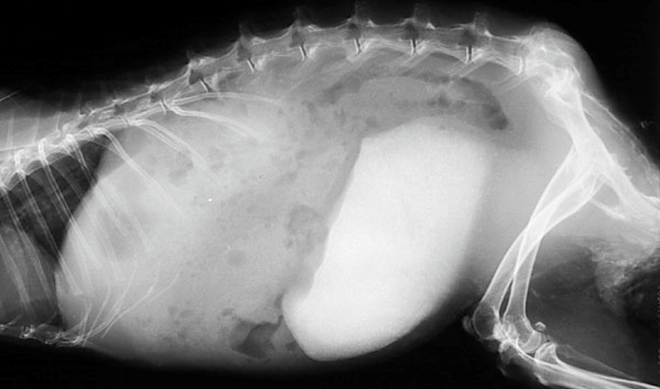

診断の第一歩は慎重な腹部触診です。膀胱アトニーの個体では、骨盤腔から腹腔のかなり前方まで達する巨大な膀胱が触知されます。神経学的検査として肛門括約筋のトーン、会陰反射、および尾のトーンを確認し、下位運動ニューロン障害の有無を評価します。炭酸カルシウムを主成分とするスラッジや結石は、X線上で鮮明な放射線不透過性(白影)として観察されます 。また、脊椎の変性、骨折、脱臼などの神経学的背景を探る上でも不可欠です。膀胱内のスラッジの流動性や、膀胱壁の厚み、層構造の維持状態を超音波検査で評価します。